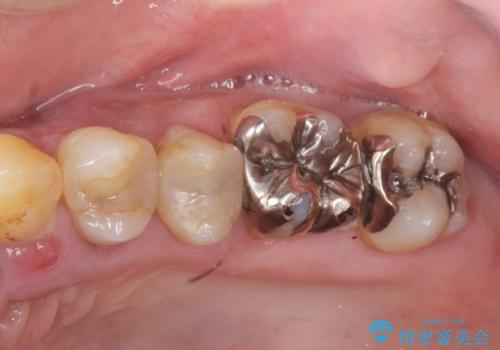

- 「全体的に歯が揺れ、今後の歯の健康に不安がある。歯周病の治療を受けたい。」、と来院されました。

精密検査の結果、重度の歯周病が認められ大きな骨の吸収を認めました。

予後の悪く保存の難しい歯を抜去し、骨の造成を含んだインプラント治療を計画します。